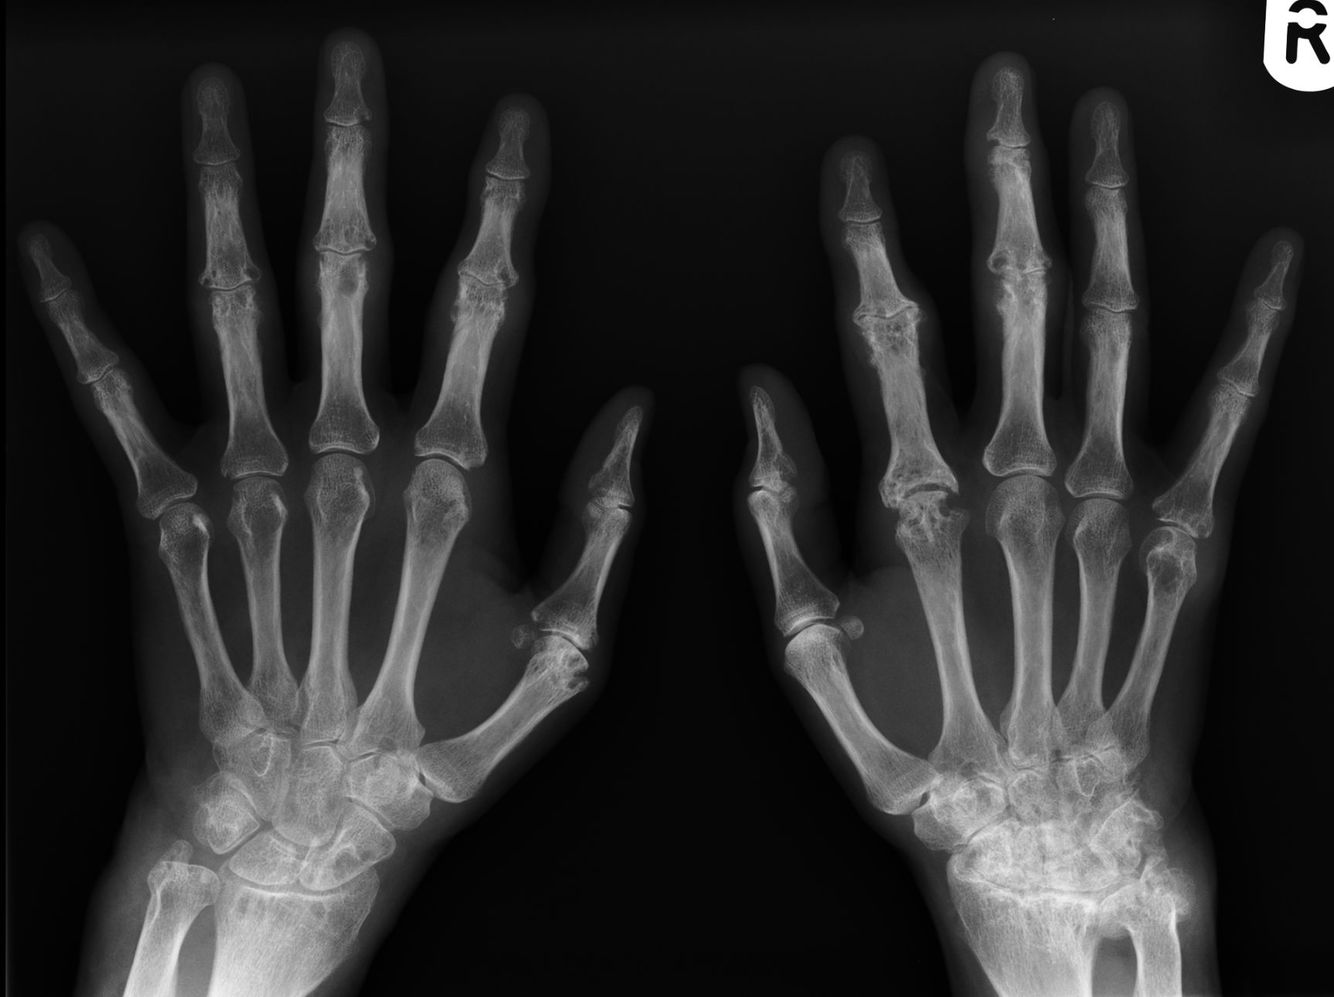

Diagnosis?

Imaging findings?

Psoriatic arthritis. Hands and feet most commonly involved. Rheumatoid factor negative, 60% HLA-B27 positive. Skin findings precede arthritis in 90%.

Periarticular marginal erosions and proliferation of bone (leads to “fuzzy” appearance). May see: pencil in cup deformity, sausage digit, “ivory phalynx-“

sclerotic distal phalanx of great toe, late- arthritis mutilans, asymmetrical sacroiliitis.